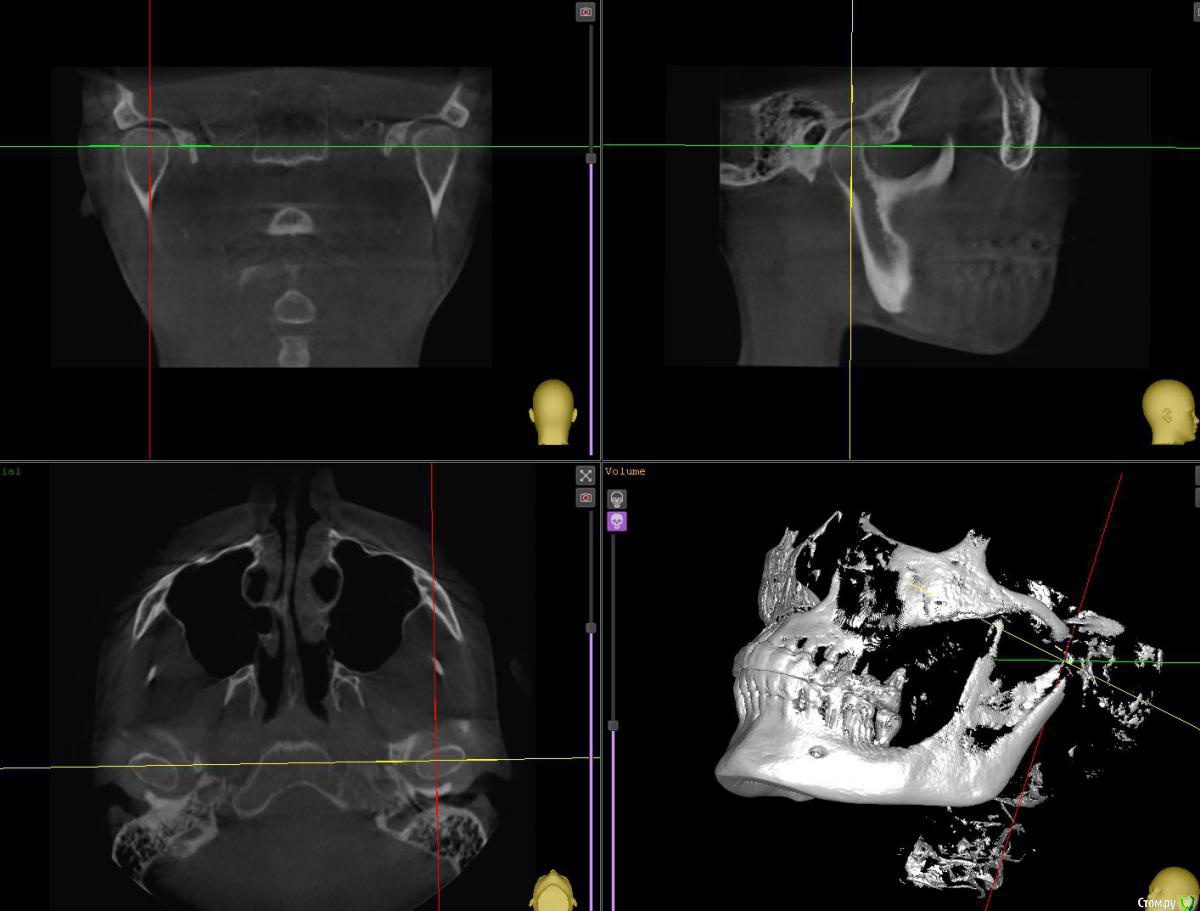

Bruks Опубликовано 29 июня, 2020 Поделиться Опубликовано 29 июня, 2020 Добрый вечер, коллегиПодскажите пожалуйста, на каком срезе нужно анализировать суставную щель в сагиттальной плоскости? Примеры далее: Ссылка на комментарий

Bruks Опубликовано 29 июня, 2020 Автор Поделиться Опубликовано 29 июня, 2020 Уточню, если непонятно выразился: Если смотреть на фронтальную проекцию КТ (окно слева вверху), то срез может быть установлен в средней или боковой части мыщелка. Это влияет на размеры суставной щели в сагиттальной плоскости (окно справа вверху). Поэтому если установить срез неправильно, то оценка положения мыщелка и суставной щели окажется искажённой. Пытаюсь найти самый правильный вариант. Спасибо 1 Ссылка на комментарий